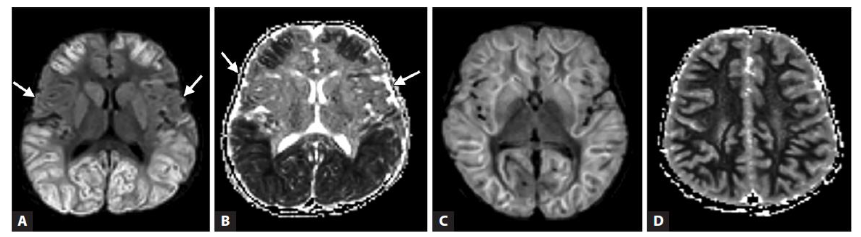

Mild encephalopathy with reversible splenial lesion (MERS) is the least severe form of ITES as the name suggests and is characterised by alteration in sensorium during a febrile illness for 1-2 days followed by improvement to baseline GCS without any long-term sequelae. During the acute phase, the imaging shows reversible lesion in the brain with restricted diffusion. Based on imaging findings, there are 2 types of MERS – Type 1 has only splenial involvement and Type 2 and splenial plus symmetric deep white matter lesions.

Familial or recurrent MERS is seen with Type 2 lesions and are associated with functional defects in MYRF gene. MYRF regulates oligodendrocyte differentiation and maintenance of myelin integrity. Therefore, defects result in encephalopathy with vacuolisation. The transient diffusion restriction seen in MERS is postulated to result from intramyelinic oedema.

MERS is characterised by reversible splenial lesions predominantly and a milder course with minimal sequelae as compared to the other ITES. DWI sequences on MRI help to identify lesions with homogenous reduction in diffusion in the corpus callosum or at least the splenium without any contrast enhancement. Those with MERS secondary to rotavirus encephalitis may progress to develop Cerebellitis and cerebellar atrophy in later stages. Takanashi et al also reported that MERS type 2 lesions tend to resolve to MERS 1 in the initial 1-2 days before complete resolution by day 7 of illness.

MERS is characterized by reversible splenial lesions predominantly and a milder course with minimal sequelae as compared to the other ITES. DWI sequences on MRI help to identify lesions with homogeneous reduction in diffusion in the corpus callosum or at least the splenium without any contrast enhancement. Those with MERS secondary to rotavirus encephalitis may progress to develop cerebellitis and cerebellar atrophy in later stages. Takanashi et al also reported that MERS type 2 lesions tend to resolve to MERS 1 in the initial 1–2 days before complete resolution by day 7 of illness²⁹.